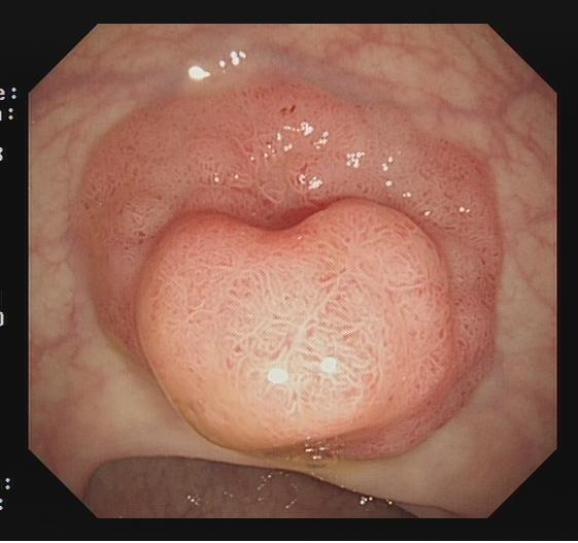

图2 小型Ⅰsp 型病变热圈套切除示意图

适用于不同大小隆起型病变Ⅰp型、Ⅰsp 型以及小型(<2 cm)Ⅰs型(具体分型标准可参照)病变的切除。小型Ⅰp型病变,圈套切除相对简单,可采用冷或热圈套切除,切除时应在保证完整切除病变同时,保留一定长度的蒂部或与肠壁保持一定距离,收紧圈套后,应抖动圈套器,观察有无周围正常肠黏膜一并套入,防止损伤肠壁。

冷/热圈套切除法